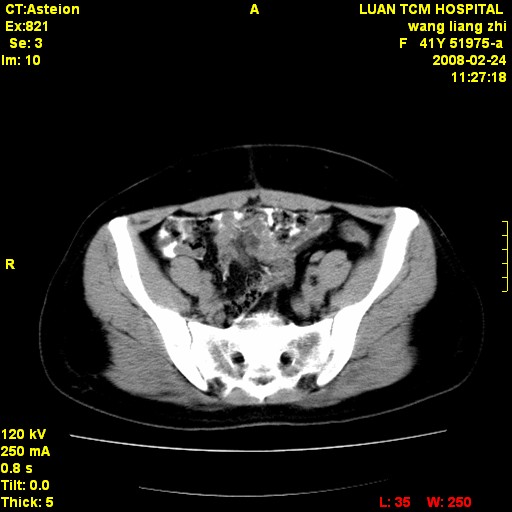

以下是引用dyqct在2009-8-23 16:17:00的发言:[br]考虑:1、造影剂进入腹腔、结肠旁沟、肝周;[br] 2、子宫明显增大(腺肌增生症?);[br] 3、膀胱显影是由于造影剂吸收后经肾分泌进入膀胱的;[br] 4、建议mri检查子宫。

以下是引用zjzjr在2009-8-23 17:28:00的发言:[br]考虑:1、造影剂进入腹腔、结肠旁沟、肝周;[br] 2、子宫明显增大(腺肌增生症?);[br] 3、膀胱显影是由于造影剂吸收后经肾分泌进入膀胱的;[br] 4、建议mri检查子宫。